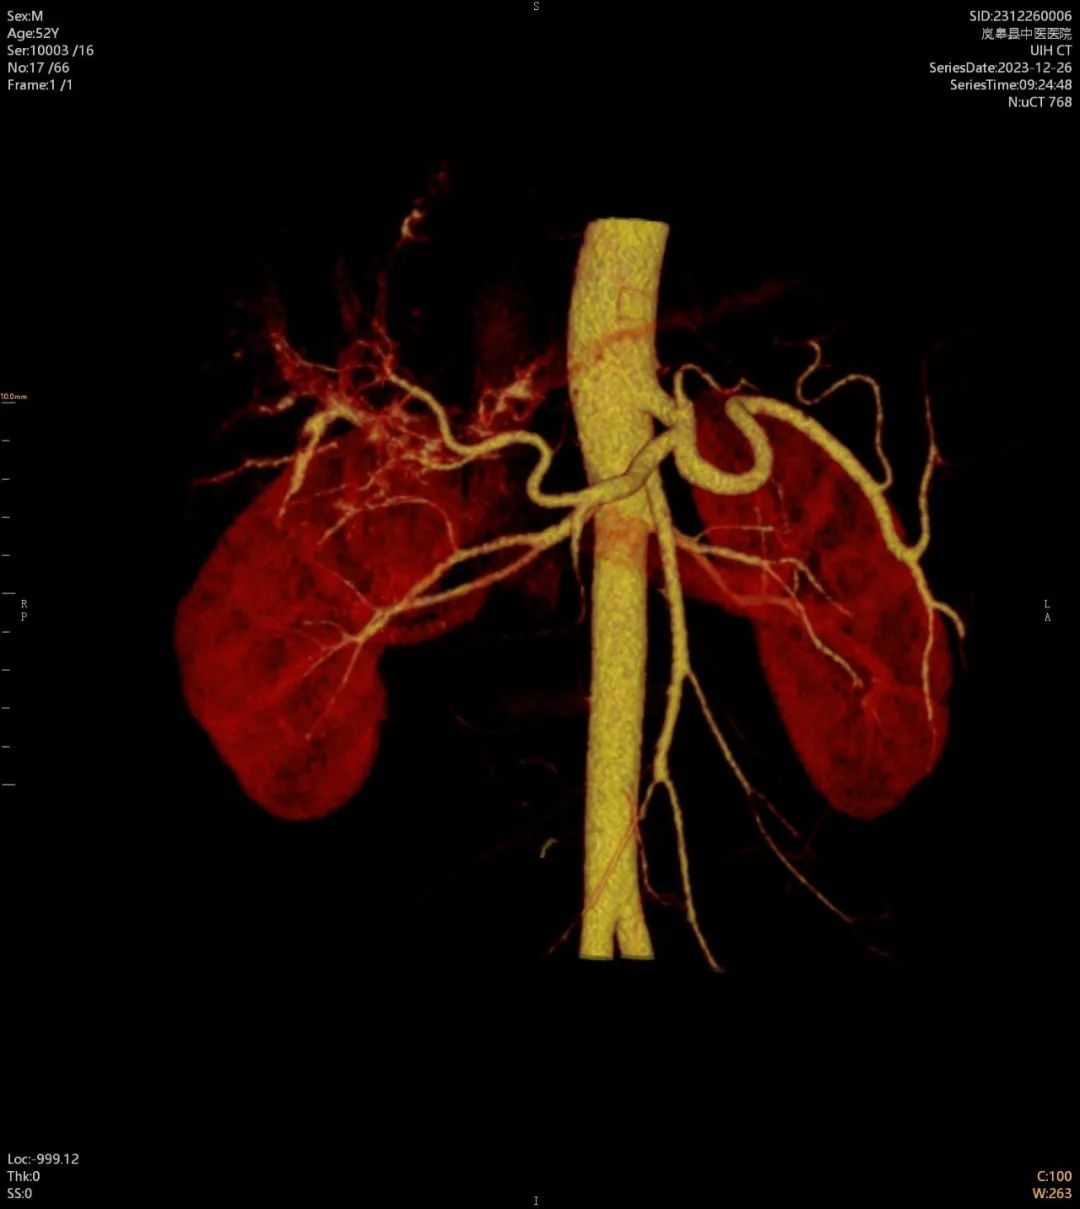

近日,在西安市中医脑病医院派驻的影像科专家任小军的指导下,岚皋县中医医院放射科成功开展了首例CT增强扫描及CT血管造影(CTA)新技术,填补了该院影像技术上的一项空白,提升了疑难疾病的诊断能力。

医院新购置的80排160层螺旋CT是“岚皋县2023年十大民生实事之一——“中医院基础服务能力提升”项目,该项目于11月初全部完成。该设备具有扫描速度快,检查范围大,图像质量高,辐射危害小等显著特点,可对全身各部位进行常规平扫、增强检查,并且可以提供冠脉CTA、头颈CTA、全身大血管CTA、全脑灌注检查等高级临床应用,为临床提供更加丰富、更加可靠的诊疗依据。同时,在对口支援帮扶专家的技术支撑下,有效的保障了每一例影像检查的准确性。

岚皋县中医医院CT增强扫描及CT血管造影(CTA)技术的成功开展,让群众不出县、在家门口就可以享受到优质、高效、便捷的影像诊断服务,减少了患者外出看病的经济负担及时间成本,标志着该院影像诊断技术水平迈上了新台阶。(供稿:岚皋县中医医院)